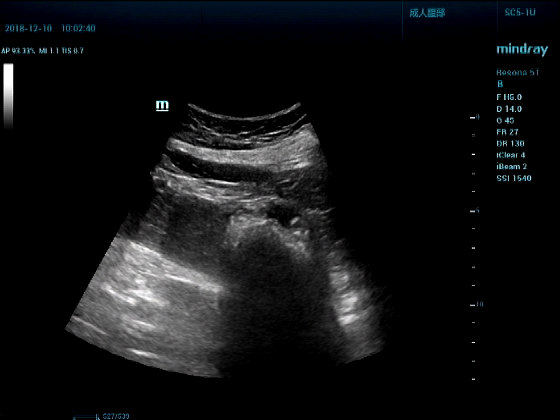

病例一:女,53岁,胃部不适一周来诊

超声可见:胃腔内见一小鸡蛋大强回声团块,后方伴强声影,位置活动。

问及病史吃山楂,柿子。

超声提示:结合临床考虑胃结石,治疗后复查